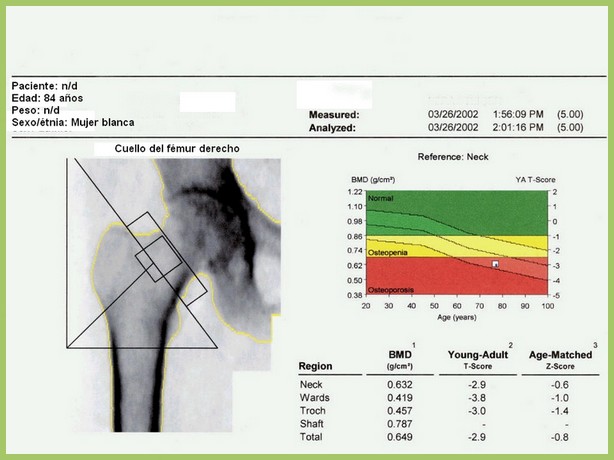

En este estudio argentino, la mitad de las densitometrías se pidieron en mujeres que no cumplían los criterios recomendados de edad o de riesgo aumentado para justificar el rastreo de osteoporosis. Salud Colectiva, octubre de 2016